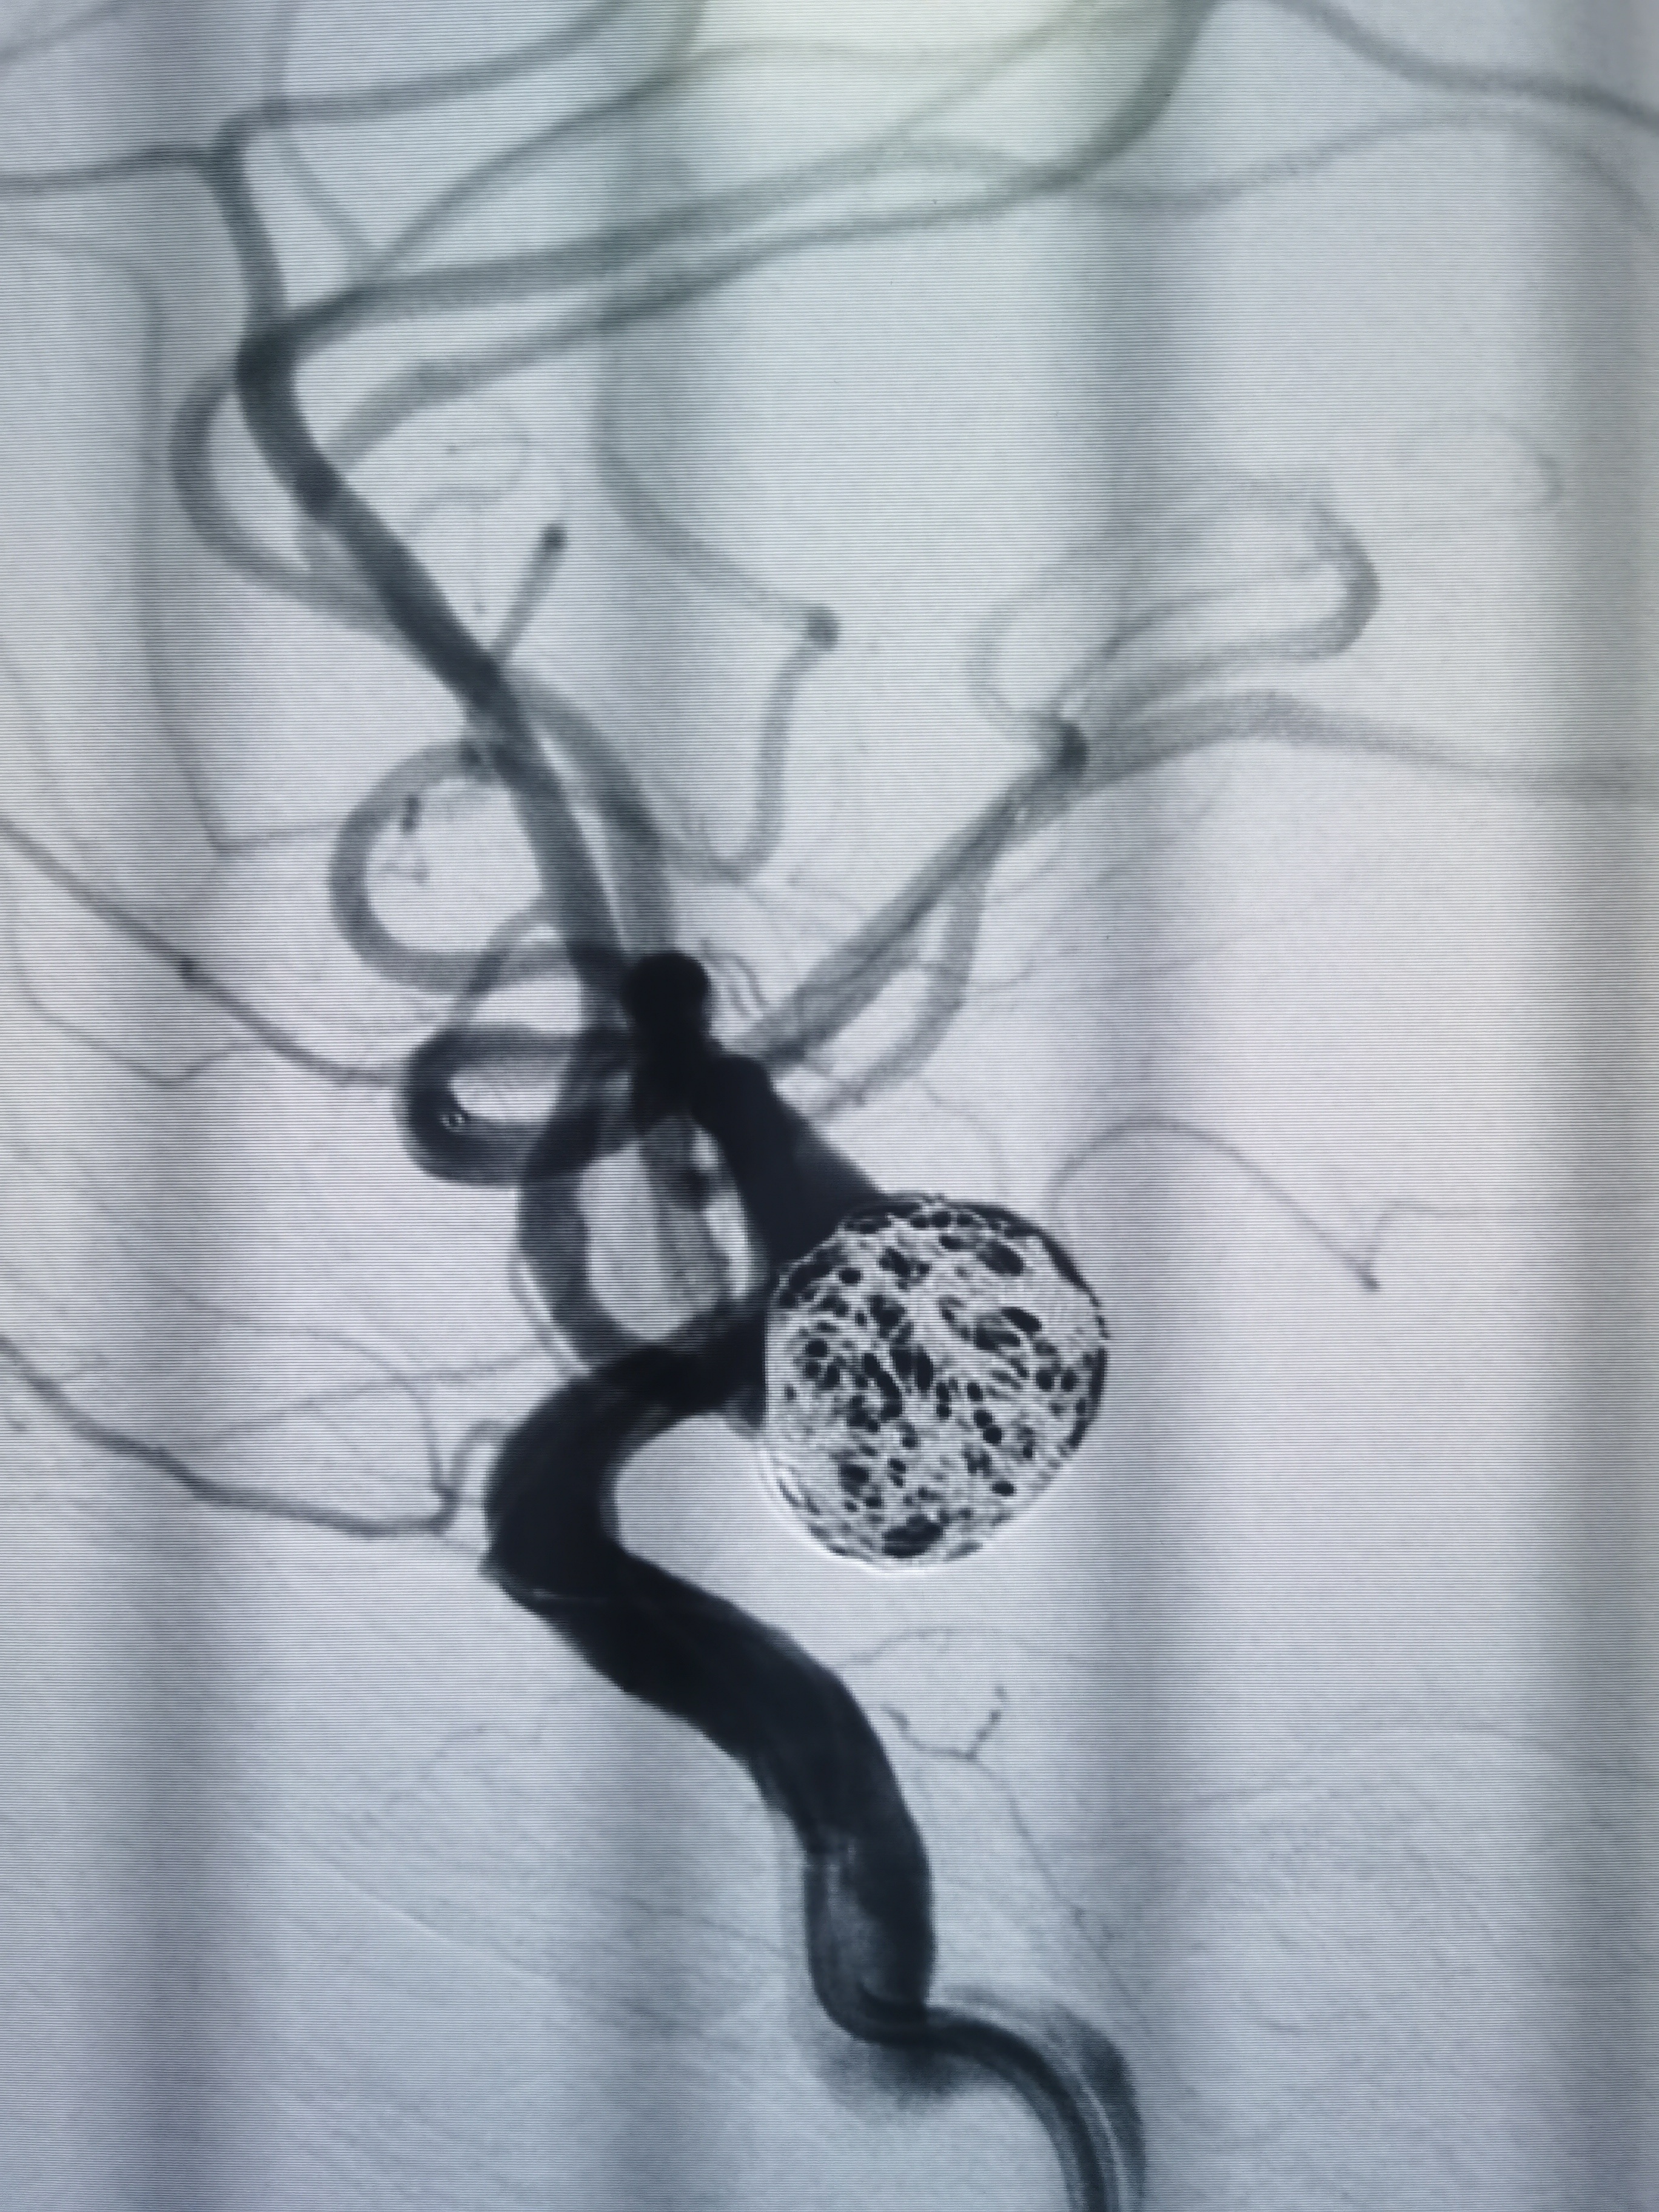

术后即刻造影见动脉瘤栓塞较完全。

术后造影见动脉瘤栓塞较为完全,载瘤动脉通畅,遂未再植入支架,逐渐撤出各级导管,缝合股动脉结束手术。